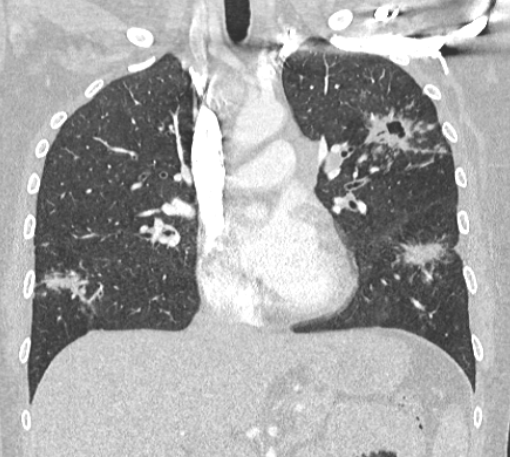

轴位HRCT示左肺上叶可见星系征,中央可见空洞。

冠状位重建HRCT示多个结节影被多个淋巴分布的微小结节包围,呈现“星系征”外观。

冠状面 MIP 重建示“星系征”。

本例患者表现为急性多系统结节病,肺部受累伴典型异常,以及左上叶空洞性结节伴“星系征”。

这种类型的结节由众多小尺寸结节汇聚而成,周围环绕着微小的卫星结节,形成独特的“星系征”。